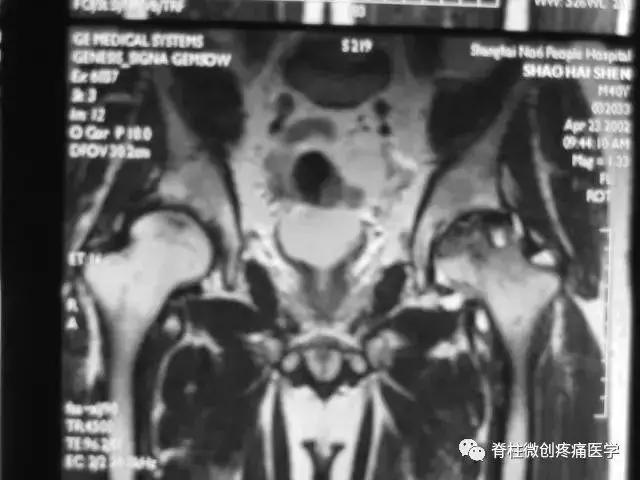

■ Ⅳ期

关节软骨彻底破坏,髋关节间隙狭窄,合并关节退行性改变。

髋臼面软骨下骨质可出现囊性变,髋臼缘骨赘增生。

股骨头因骨坏死、囊变、骨折而显著塌陷、变形,受累范围可局限于股骨头上部或累及整个股骨头。

股骨头出现分节碎裂、骨折移位。